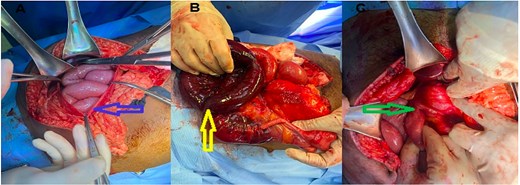

Gentle traction failed to reduce the bowel due to the narrow neck and the overlying IMV. After confirming adequate collateral venous flow, the IMV was safely divided, allowing complete reduction of the herniated jejunum. The bowel was viable throughout. Partial excision of the sac was performed to eliminate the excessive peritoneal pocket and reduce the recurrence risk (Fig. 2).

(A) Hernial sac containing bowel (black arrow), (B) IMV (blue arrow), (C) after divison of the IMV (yellow arrow).

Upon opening the hernia sac, ~100 cm of terminal ileum was found to be dusky, congested, and non-viable, confirming ischemia secondary to incarceration. The DJ junction was noted to lie to the right of the midline—an anatomical indicator of associated intestinal malrotation (Fig. 4).

(A) Opened hernial sac with bowel content, (B) ischemic bowel, (C) Duodeno-jejunal junction (DJ) on right side.